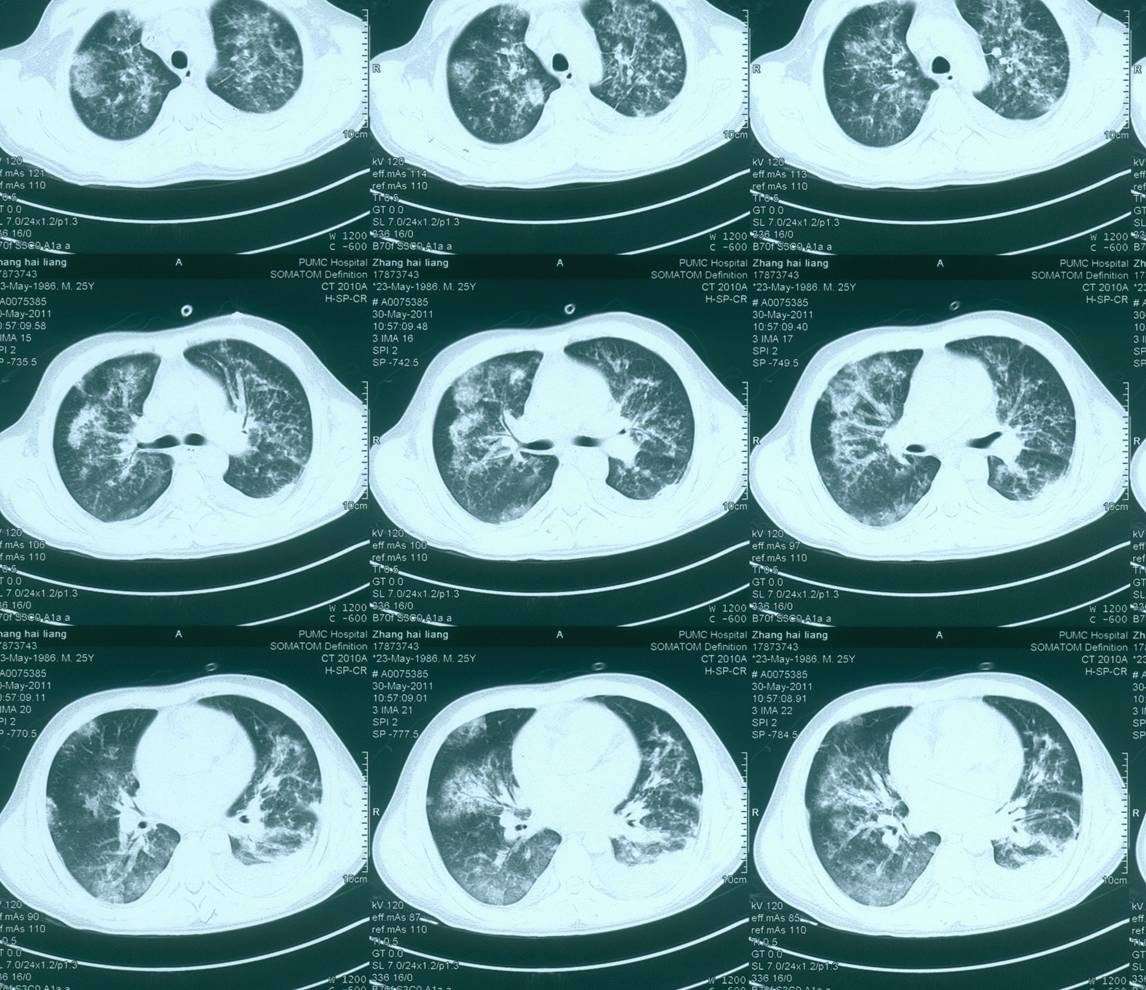

◆胸部CT:双肺实变,双侧胸腔积液伴双肺膨胀不全,心衰可能

——复查胸部CT是双肺内新发斑片影

2天后复查CT:双肺渗出病灶明显吸收

◆胸部CT提示始于上肺的弥漫性双肺渗出性病变